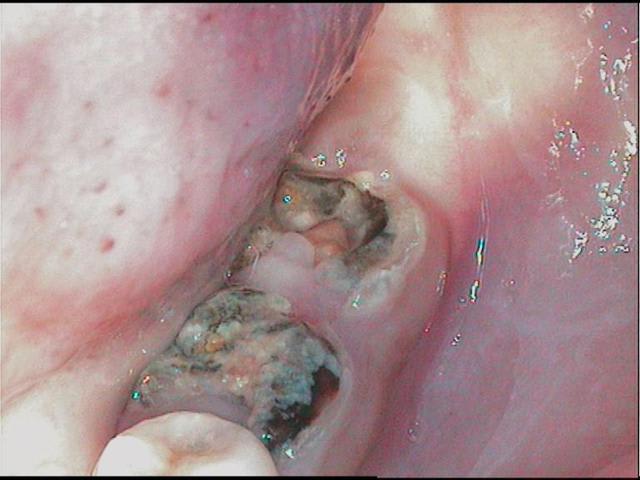

13 ans, je vous livre en vrac et dans n'importe quel sens

je m'en vais donc naviguer quelques temps entre pulpites et nécroses, calmer les pleurs, resorber les granulomes, ré équilibrer le "risque carieux"

j'ai passé les détails, aucune dent indemne de toute manière, tout est comme ça , les inc md itou

techniquement je dois etre loyal, les photos font reculer, j'ai reculé aussi en bouche, mais c'est plus impressionant au premier abord, dans le détail tout peut se jouer comme le montre cette radio

alors: les pulpites et granulomes en prems, ensuite les endos inévitables, ensuite des verre iono ou eugenates partout, ré équilibrer le risque et motiver, ensuite caler l'occlusion avec les 8 pm dans un premier temps(parceque là j'y pige rien) ensuite l'ortho (parceque là c'est pas présentable)enfin toutes ces sortes de chose quoi...